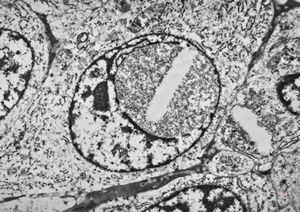

M,50y. | Pneumocystis carinii - lung